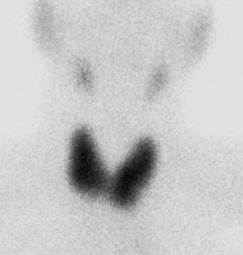

- Age/Sex: 82M

- Chief Complaint: 側傫偲側偔懱偑偩傞偄

- Clinical Course

- 15擭慜 complete AV block偱pacemaker怉偊崬傒

- 嶐擭6寧 COPD偵懳偟偰嵼戭巁慺椕朄

- 嶐擭7寧 寫懹姶弌尰

- 嶐擭8寧 撪壢傊擖堾

- 峛忬態惛嵏偺偨傔I-123峛忬態僔儞僠僌儔僼傿傪梊掕偟偰偄偨偑姵幰偺帠忣偵傛傝戅堾偡傞偙偲偲側偭偨丅

- 戅堾慜偵99mTcO4偵曄峏偟偰峛忬態僔儞僠僌儔僼傿傪巤峴偟偨丅

- Lab. data

- TP:7.8g/dl, T-Bil:1.00mg/dl, ALP:329 IU/L, LAP:66 IU/L,

兞-GTP:114 IU/L, CHE:94IU/L, AST:77.4 IU/L, ALT:40 IU/L,

LDH:140.8 IU/L

- CPK:911IU/L, CPKMB:25.8IU/L

- WBC:3200/兪L, RBC:369枩/兪L, Hb:12.0g/dl, Hct 37.4%, Plt

14.9枩/兪L, CRP 0.1mg/dl

- TSH: 179.76兪U/ml, FT3 0.77pg/ml, FT4 0.66ng/dl,

microsome test 409,600, Anti-TPO Ab >50, Anti-Tg Ab

>100

- Images

- Tc-99m scan: uptake 6.8%

- neck CT